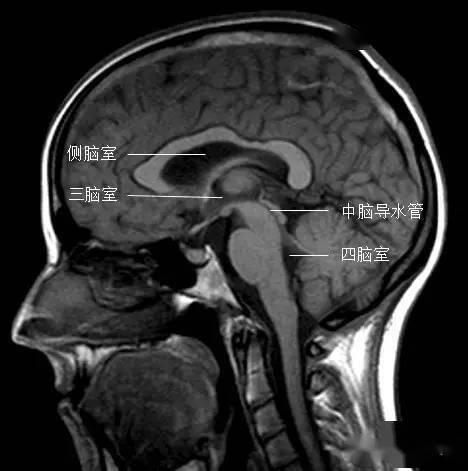

冠状位矢状位三脑室在哪

图片尺寸468x471